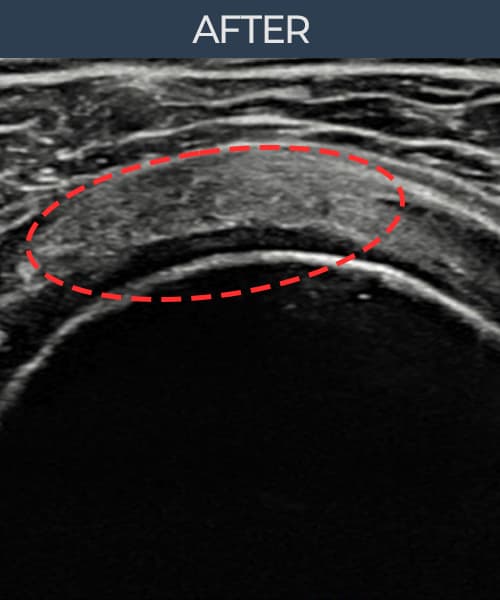

実際の患者様の施術前後の超音波画像。

手術なしで実現できる回復をご確認ください。

[経過期間: 24.07.10~24.09.18]

[縫縮術] 超音波検査にて右 棘上筋腱 関節面側断裂進行型(12mm × 7mm (腱厚の約55%欠損))を確認。縫縮術施行後、腱の連続性が回復し、日常生活に復帰されました。